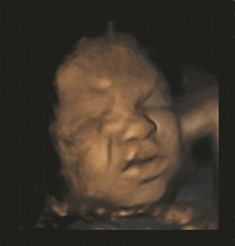

32 week old fetus showing pain

We use cookies to ensure that we give you the best experience on our website. You can change your cookie settings at any time. Otherwise, we'll assume you're OK to continue. Unborn babies 'practise' facial expressions in the womb Unborn babies 'practise' facial expressions of pain in the womb, according to a study published today. The researchers from Durham and Lancaster Universities suggest that fetuses' ability to show a "pain" facial expression is a developmental process which could potentially give doctors another index of the health of a fetus. The study extends the findings of previous work demonstrating that the facial expressions of healthy fetuses develop and become more complex during pregnancy resulting in fetuses being able to show recognisable facial expressions. The 4D scans of 15 healthy fetuses showed that they develop from making very simple one-dimensional expressions at 24 weeks, such as moving their lips in order to form a "smile", to complex multi-dimensional expressions which can be recognised as "pain" expressions, by the time the mother is 36 weeks into her pregnancy.